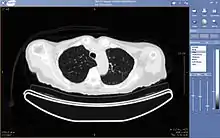

رادیولوژی از راه دور (به انگلیسی: Teleradiology)، شاخه ای از پزشکی از راه دور است که در آن، از فناوری اطلاعاتی و ارتباطاتی برای انتقال تصاویر رادیولوژی از یک مکان به مکان دیگر استفاده میشود. هدف از این کار، به اشتراک گذاری تصاویر با سایر رادیولوژیستها و پزشکان است تا امکان تشخیص، مشاوره و تفسیر از راه دور تصاویر رادیولوژی فراهم گردد. این روش میتواند برای تفسیر مطالعات تصویر برداری غیر تهاجمی مانند تصاویر دیجیتال اشعه ایکس، سی تی اسکن، ام آر آی، سونوگرافی و پزشکی هسته ای مورد استفاده قرار گیرد.[1]

همچنین از جمله متداولترین فناوریهای تصویر برداری که میتواند به صورت از راه دور انجام شود میتوان به رادیولوژی، سونوگرافی، فلوروسکپی، سی تی اسکن، ام آر آی و پزشکی هسته ای اشاره نمود[2]

مشاهده تصاویر، نیاز به یک ایستگاه کاری دارد که قابلیت نمایش تصاویر با وضوح بالا را داشته باشد. امروزه انواع مختلفی از نرمافزارهای متن باز و تجاری در دسترس هستند که امکان مشاهده، دستکاری، اندازهگیری، بازسازی سه بعدی تصاویر و موارد دیگری را فراهم میسازند[7]